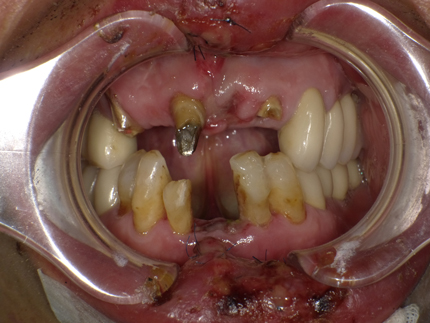

通院患者様が自転車転倒事故にて前歯5本破折や脱落の受傷する(2018年5月17日)

(受傷翌日来院時口腔内外写真)

受傷前の口腔内写真(2012年8月6日 前歯部治療終了時写真)